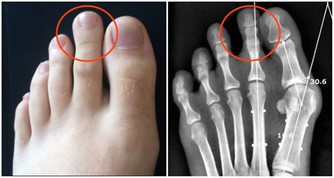

在人類種係發生和演化過程中,食物種類的日趨精細,帶來了咀嚼器官的退化,造成頜骨長度與牙列所需長度的不協調,結果是頜骨慢慢退化,逐漸縮小,而牙齒本身的大小並沒有改變。但是,智齒是牙列中最後萌出的牙齒,當智齒萌出時,往往因為萌出位置不足,導致程度不同的阻生。

近中或水平智齒常常造成牙列擁擠,開頜。當開閉口有彈響、疼痛等顳頜關節紊亂綜合症,智齒常是「肇事者」之一。